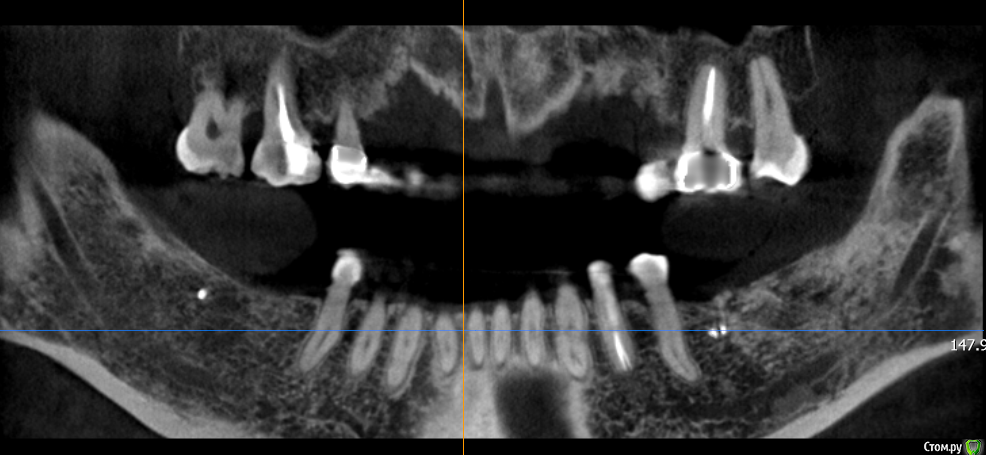

Mane Опубликовано 22 декабря, 2014 Поделиться Опубликовано 22 декабря, 2014 в целом хорошо. но нет деталей где я смогу понять что качественно отработали: 1) кт срезы до и после с замерами чтоб было понятно на сколько нарастили 2)кт срезы с установленными имплантами чтоб было понятно какие болты удалось установить и стало чтоб всем понятно для чего наращивали - ведь вы растили в высоту и в ширину. 3) фото на этапе установленных имплантов - соотношение платформы импланта и уровня кости - заглубили или нет - если да то насколько. Ориентировались ли на будущий зенит зуба. мне понравилось. но чуйка что есть гиперлечение - думаю можно было болты и костную пластику совместить. Растить по высоте я скорее всего бы не стал. 1 Ссылка на комментарий

SDC Опубликовано 22 декабря, 2014 Поделиться Опубликовано 22 декабря, 2014 Через 5 месяцев...Мне не понравилось просветление в 3 квадранте. Крутили КТ? Что это? Ссылка на комментарий

Dantist55 Опубликовано 22 декабря, 2014 Автор Поделиться Опубликовано 22 декабря, 2014 в целом хорошо. но нет деталей где я смогу понять что качественно отработали: 1) кт срезы до и после с замерами чтоб было понятно на сколько нарастили 2)кт срезы с установленными имплантами чтоб было понятно какие болты удалось установить и стало чтоб всем понятно для чего наращивали - ведь вы растили в высоту и в ширину. 3) фото на этапе установленных имплантов - соотношение платформы импланта и уровня кости - заглубили или нет - если да то насколько. Ориентировались ли на будущий зенит зуба. мне понравилось. но чуйка что есть гиперлечение - думаю можно было болты и костную пластику совместить. Растить по высоте я скорее всего бы не стал.КТ посмотрю позже на работе - я в отпуске.По высоте добавляли чтобы зубы не получились большими.Импланты не заглублял, т.к. у XIVE полированная фаска.Насчет гиперлечения может Вы и правы. Эту работу я сделал сразу после приезда от Кури. 2 Ссылка на комментарий

Dantist55 Опубликовано 22 декабря, 2014 Автор Поделиться Опубликовано 22 декабря, 2014 Мне не понравилось просветление в 3 квадранте. Крутили КТ? Что это?Перед имплантацией крутил-все было норм. Ссылка на комментарий